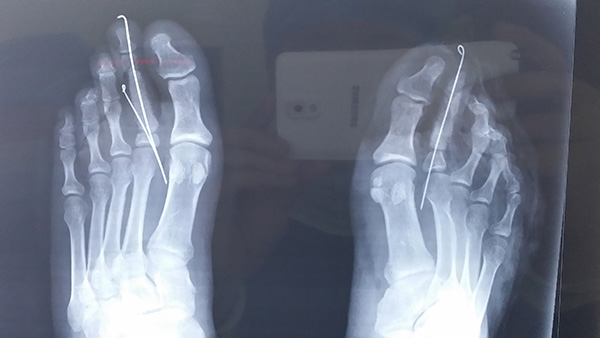

拇指Ⅳ度再造

拇指Ⅴ度再造